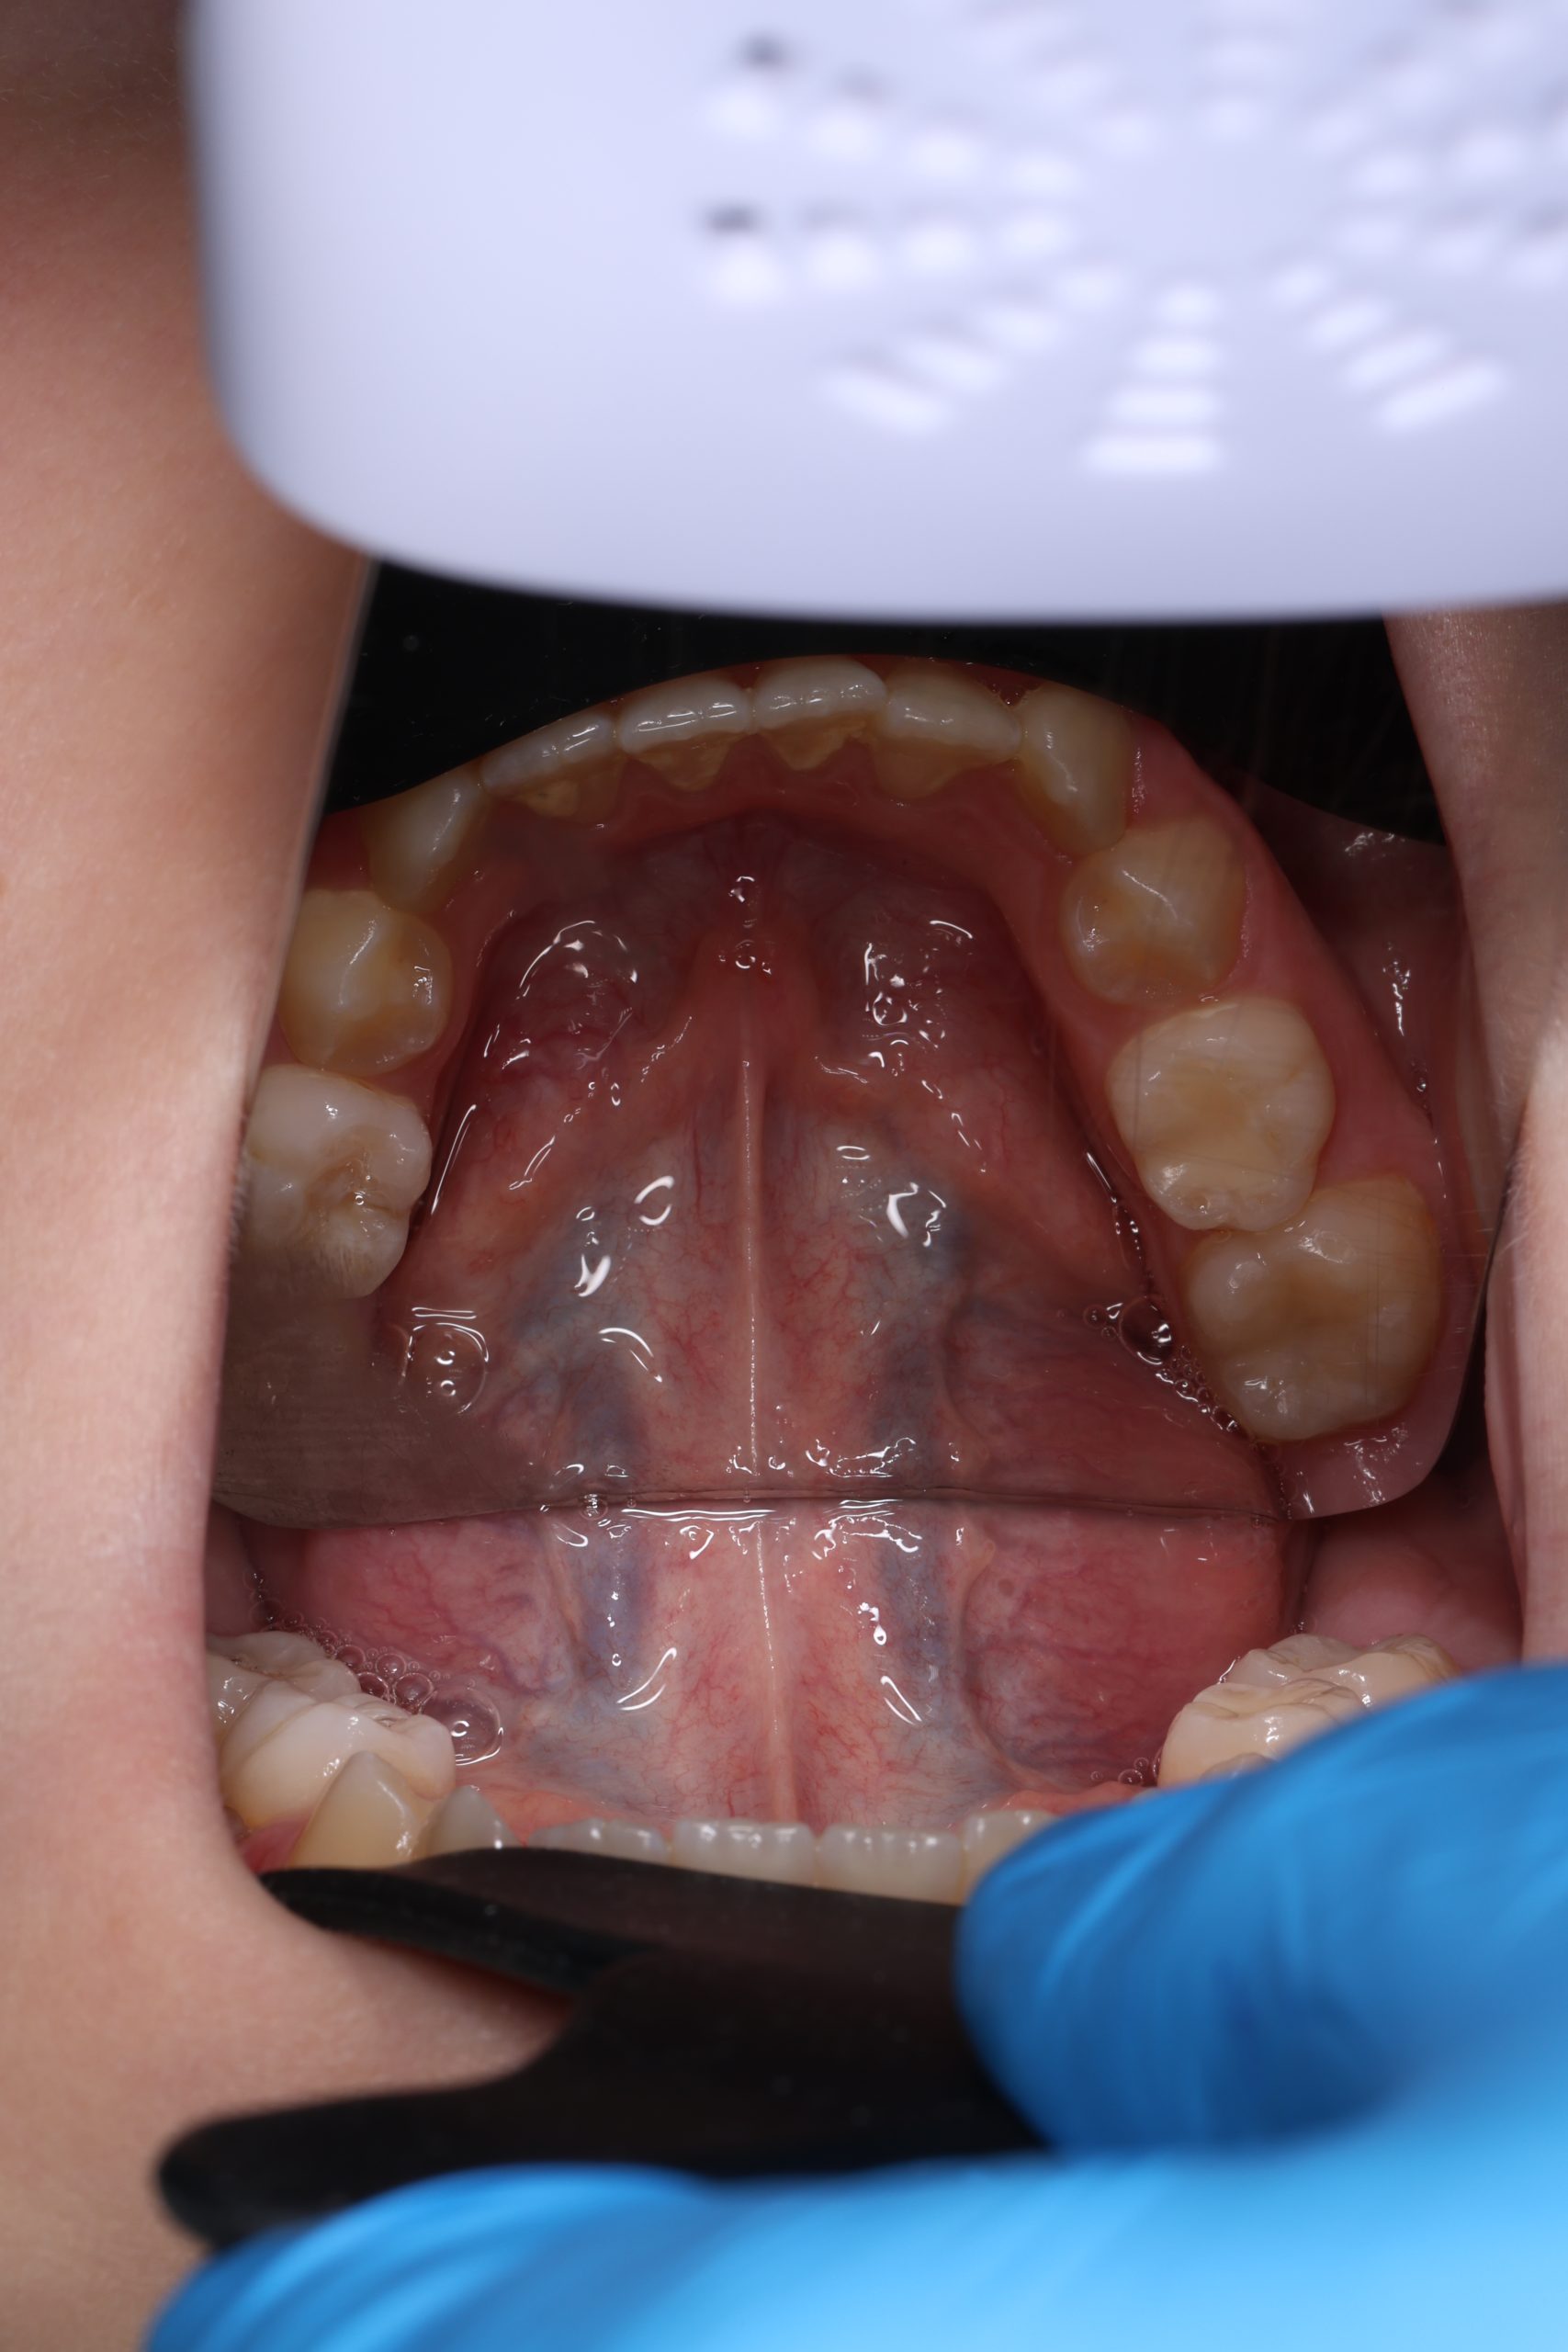

We examine the condition of teeth, gums, and bite. - Plaque Disclosure with Special Indicators

Areas that weren’t cleaned well appear purple. The darker the shade, the older the plaque. This helps both kids and parents understand where brushing needs to improve. - Brushing Training & Home Care Tools Selection